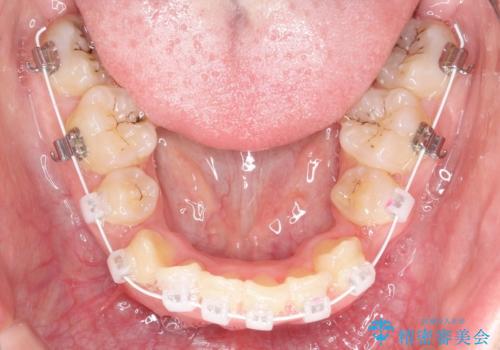

- 審美

上下左右の前から4番目の歯を抜歯をして、ワイヤー矯正にて並べる計画としました。

患者様が装置を早期に除去したいという希望もあり、少々下の前歯のがたつきが残った状態で矯正を終了しました。